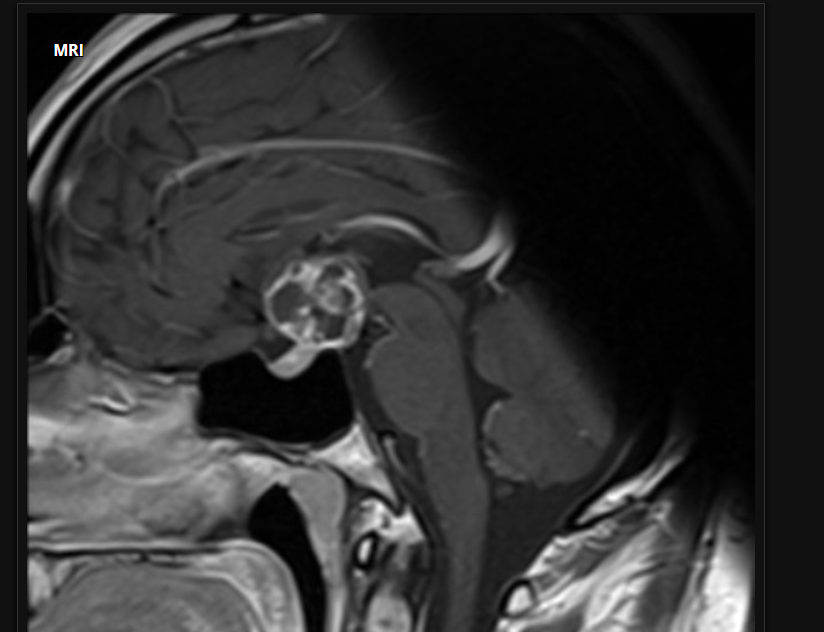

Q

35 anos, Masculino

A

Craniofaringioma adamantinomatoso

Craniofaringioma adamantinomatoso Crianças Lesão suprasselar com componente sólido e cístico; lobulado; calcificação anelar ou nodular presente em quase TODOS os craniofaringeomas pediátricos; Componente cístico proeminente e componente sólido pequeno, mas com realce.